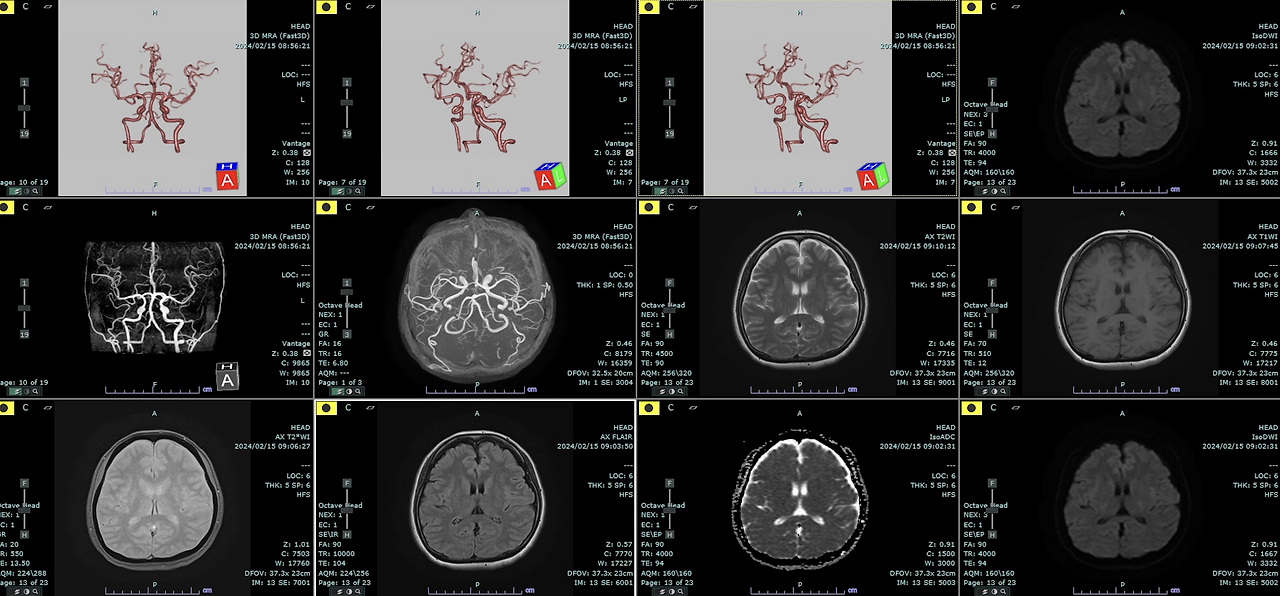

뇌 MRI는 두통, 어지럼, 시야 이상, 마비감 같은 신경학적 증상이 있을 때 원인 감별에 자주 쓰이는 대표 영상검사입니다. 다만 “비용이 얼마나 나오나”, “촬영은 몇 분 걸리나”, “금식이 필요한가”처럼 검사 전 단계에서 가장 많이 막히는 포인트가 늘 비슷합니다. 특히 뇌 MRI는 건강보험 적용 여부(급여/비급여), 조영제 사용 여부, 촬영 프로토콜, 병원 종별(의원-병원-종합병원-상급종합병원)에 따라 체감 비용과 대기-검사 시간이 크게 달라져서, 같은 ‘뇌 MRI’라도 결과적으로는 전혀 다른 경험이 될 수 있습니다.

- 검사 범위(뇌 MRI 단독 vs 뇌 MRI+뇌혈관 MRA 동시 촬영)

- 뇌 MRI+뇌혈관 MRA 동시: 촬영 항목이 늘어 총 촬영 시간이 증가할 수 있음